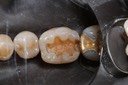

Gary Umeda #18,19,20 pre-op

Gary Umeda #18, 19, 20 prep